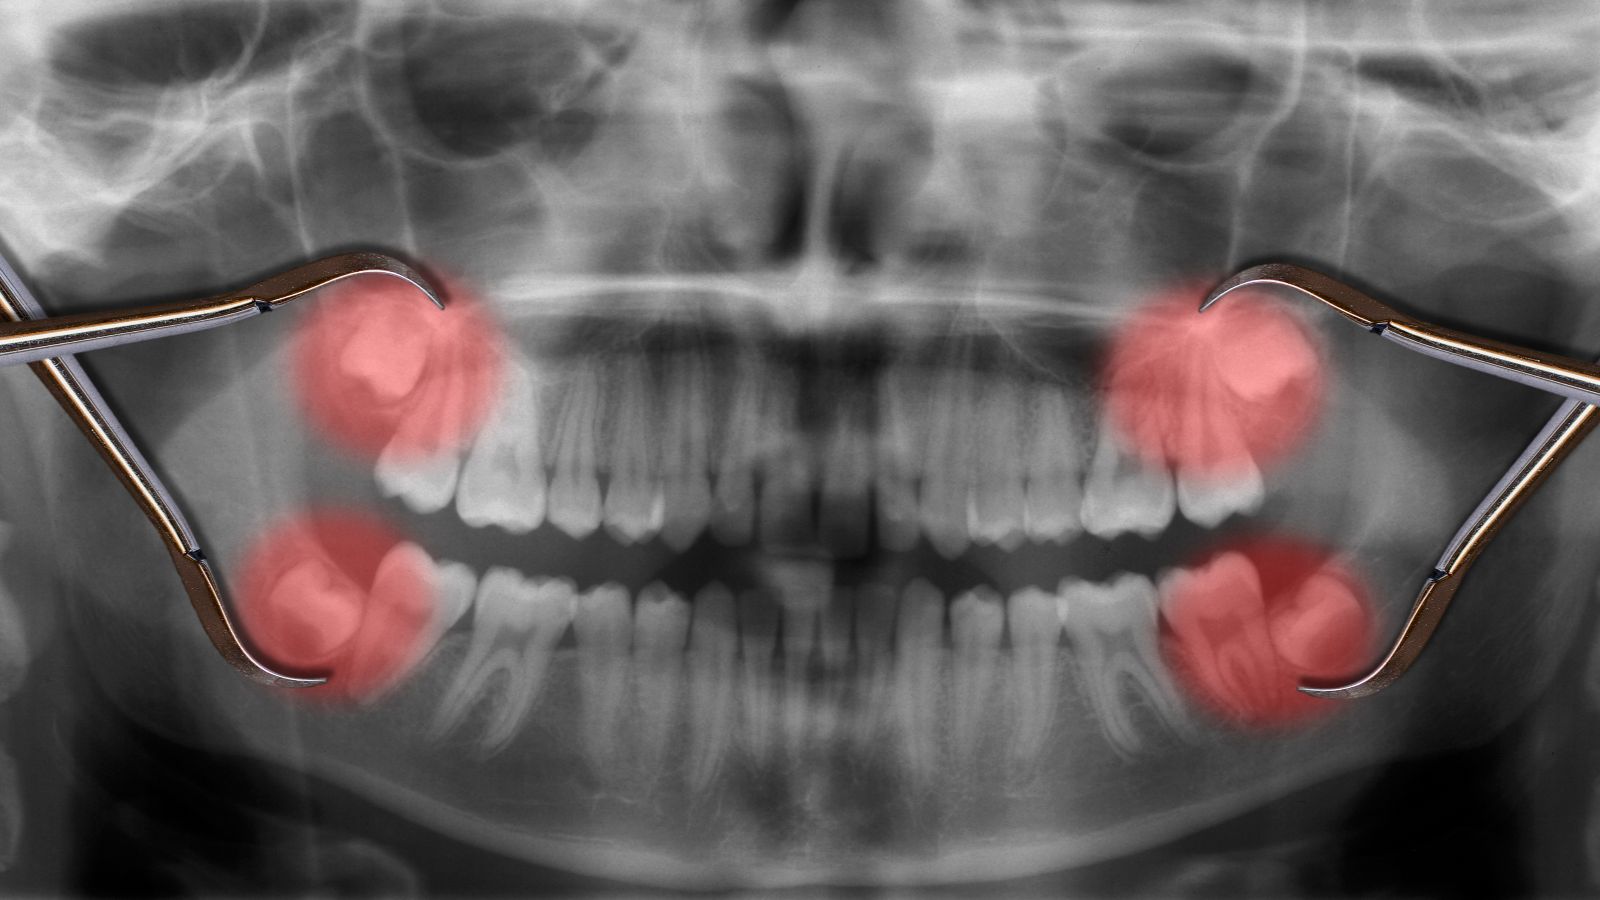

کشیدن دندان نهفته؛ یک ماجرای پیچیده‌تر

کشیدن دندان نهفته یک جراحی دندان پیچیده‌تر است که برای دندان‌هایی انجام می‌شود که به طور کامل از لثه خارج نشده‌اند یا زیر خط لثه شکسته‌اند. دندان عقل شایع‌ترین نمونه دندان نهفته است که به دلیل کمبود فضا در فک، نمی‌تواند به درستی رشد کند و باعث درد، عفونت و آسیب به دندان‌های مجاور می‌شود.

این عمل معمولاً توسط جراح دهان و فک و صورت انجام می‌شود. در این نوع، جراح برشی کوچک در لثه ایجاد می‌کند تا به دندان و استخوان اطراف آن دسترسی پیدا کند. گاهی برای خروج راحت‌تر، لازم است مقداری از استخوان پوشاننده دندان برداشته شود یا دندان به قطعات کوچک‌تر تقسیم گردد. این فرآیند با دقت بالا انجام می‌شود تا سلامت شما تضمین شود.